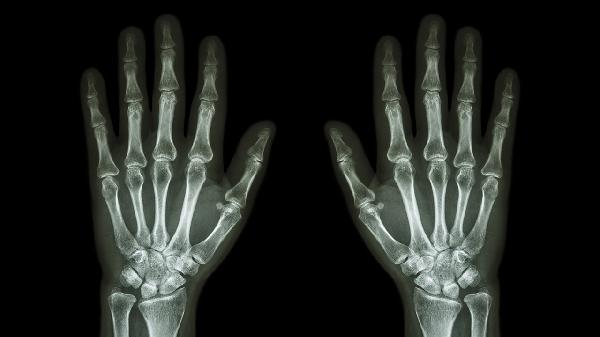

关节软骨磨损导致骨面直接摩擦,弹响伴随晨僵和活动后疼痛。X线可见关节间隙变窄。可遵医嘱使用双氯芬酸钠缓释片、硫酸氨基葡萄糖胶囊、塞来昔布胶囊等药物,配合关节腔注射治疗。